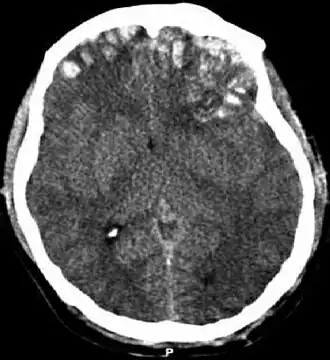

La lesión difusa se circunscribe básicamente a la lesión axonal difusa (LAD) y a algunos casos de tumefacción cerebral difusa (swelling). Una LAD es el corte de los axones en la sustancia blanca cerebral lo que causa la aparición déficits neurológicos no lateralizados como la encefalopatía. Las consecuencias de este tipo de lesión pueden tener un retraso de aparición de hasta 12 horas después del trauma. La LAD se produce por efecto de fuerzas inerciales que actúan sobre los axones durante unos 50 ms en sentido lineal o angular (por ejemplo, en colisiones frontales) lo que produce la desconexión y ruptura de los axones (axotomía primaria); no obstante la mayoría de los axones dañados (94%) son afectados por la axotomía diferida que consiste en un aumento a la permeabilidad de Ca++ en los nodos de Ranvier que causa la destrucción celular por excitotoxicidad. Ambas axotomías evolucionan desfavorablemente con cambios histopatológicos progresivos como son la formación precoz de bulbos de retracción axonal, acumulación de microglia y presencia de tractos de degeneración walleriana. La LAD puede ser identificada como hemorragias petequiales en la materia blanca (especialmente subcortical) en la TC y RM después de un TCE; sin embargo, los resultados pueden aparecer sutiles o ausentes en las imágenes. Los pacientes que padecen una LAD están subreactivos desde el momento en que se inflige el traumatismo porque la afectación axonal interrumpe las señales del sistema reticular activador ascendente y sus manifestaciones van desde una conmoción cerebral hasta la lesión axonal difusa grave.[8][5]

Las contusiones se encuentran en 20% al 25% de los pacientes con TCE grave. Son lesiones heterogéneas compuestas de zonas de hemorragia puntiforme, edema y necrosis que aparecen en las imágenes de TC como áreas de hiperdensidad puntiforme (hemorragias), con hipodensidad circundante (edema), suelen estar localizadas en la cara inferior del lóbulo frontal y la cara anterior del lóbulo temporal por su relación con el ala mayor del esfenoides. También se pueden encontrar en la superficie de impacto y en la superficie contraria a este, el llamado efecto golpe-contragolpe. Cuando estas evolucionan se parecen más a los hematomas intracerebrales y su ubicación depende el posible efecto de masa.